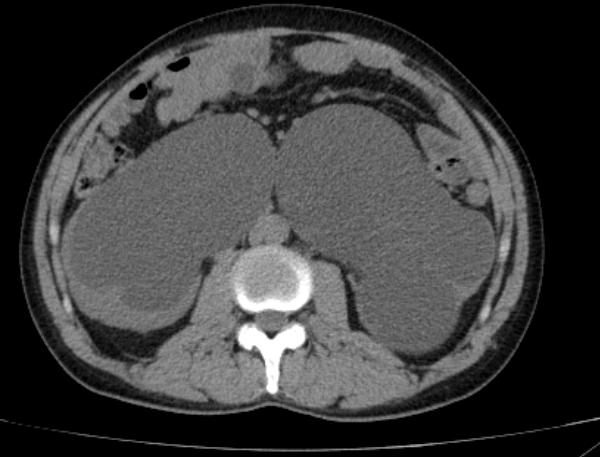

进一步完善泌尿系CT发现

患者除了双肾重度积水

输尿管扩张之外

盆腔有大量脂肪堆积

CT显示赵大哥双肾重度积水

盆腔脂肪明显增多,前列腺抬高,膀胱挤压变形